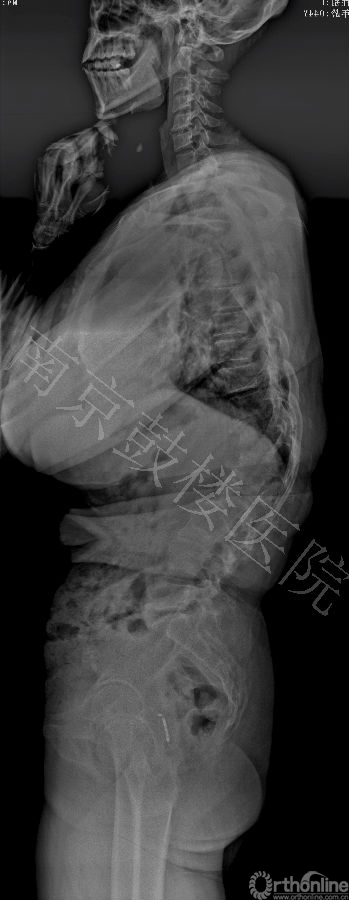

近日,南京鼓楼医院成功运用后路全脊椎截骨术和CDH Solera内固定矫形技术治疗一例先天性脊柱侧后凸成年患者。此为Solera内固定系统在中国的首例手术。

本例女,44岁,因严重的脊柱侧后凸畸形造成躯干塌陷,接受全脊椎截骨术和Solera内固定系统矫形手术,矫正率高达82%,无并发症发生。患者对手术效果非常满意。